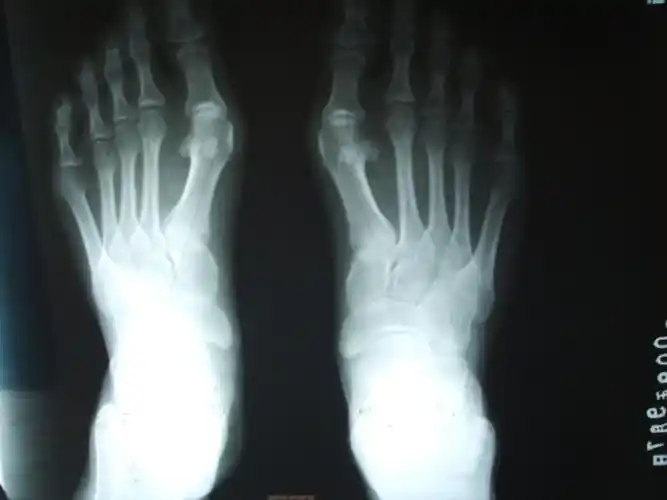

大脚骨的疼痛要如何缓解,大脚骨医生和你讲一讲,看清楚